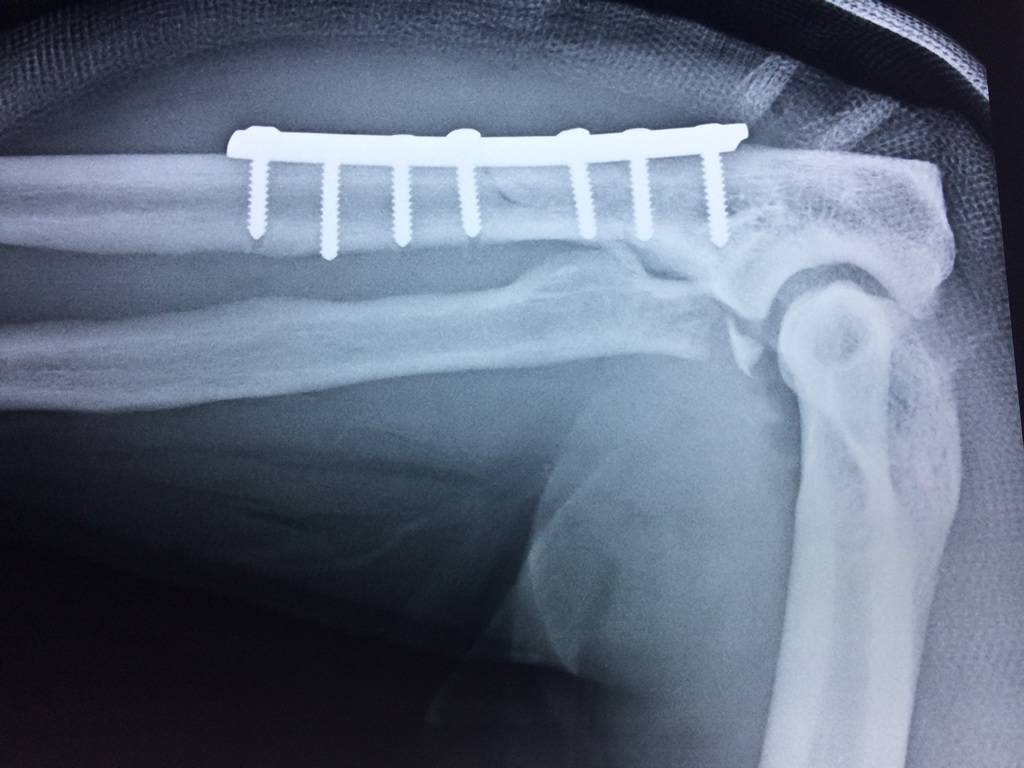

Cirugias en El Salvador - Codo

Los extremos óseos se conectan entre si por un conjunto de ligamentos que contribuyen a su fijación y están rodeado por una estructura común que se llama cápsula articular, en cuyo interior se encuentra el líquido sinovial.

En el lenguaje común se le da el nombre de codo a la parte posterior y prominente situada en la unión del brazo con el antebrazo.